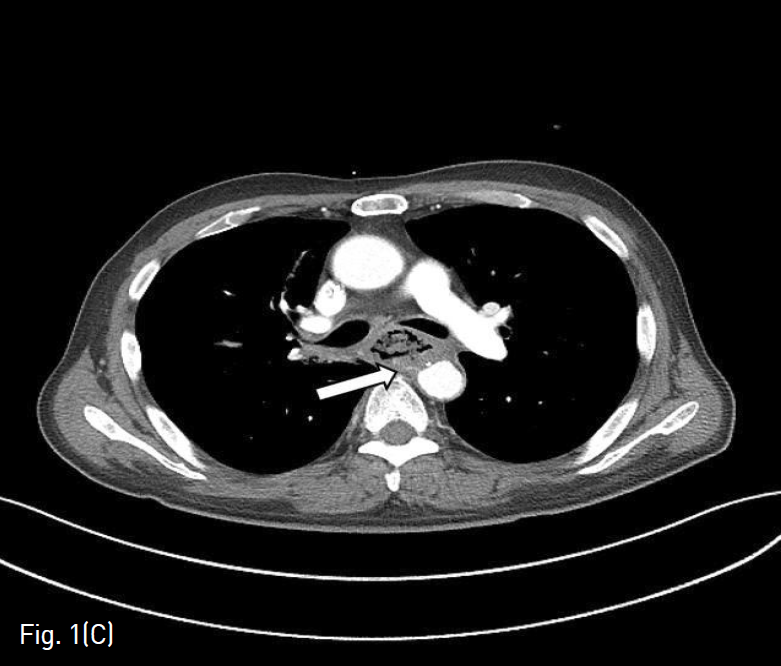

(A) This is endoscopic view of a patient with massive hematemesis. Active bleeding focus is seen in the proximal portion of the stent.

특별한 기저질환이 없던 환자로, 서서히 발생한 연하 곤란을 주소로 4개월 전 내시경 검사를 시행하였고, 식도 중부에 압박을 보이는 종괴가 있어 전원되었다. 본원에서 내시경 검사 하에 시행한 조직검사 상 편평세포암으로 진단되었고 흉부 컴퓨터단층촬영에서 해당 병변이 종격동과 기도 및 양측 주기관지를 침범한 상태였다. 환자는 고식적 치료를 위해 내시경을 통하여 식도스텐트를 삽입하였고 국소적 항암방사선 동시요법(CCRT, Concurrent chemoradiotherapy)을 시행하였다. 약 3개월 후 환자는 폐렴으로 인해 입원치료를 받았고, 입원 상태에서 토혈을 하였다. 추적 내시경 검사에서 식도 내부에 대량 출혈이 보였다 (Fig. 1A). 환자는 명치의 통증을 호소하였으며 맥박수가 100대로 상승하고 수축기 혈압이 70-80대로 낮아지는 등 활력징후상 불안정을 보였다.